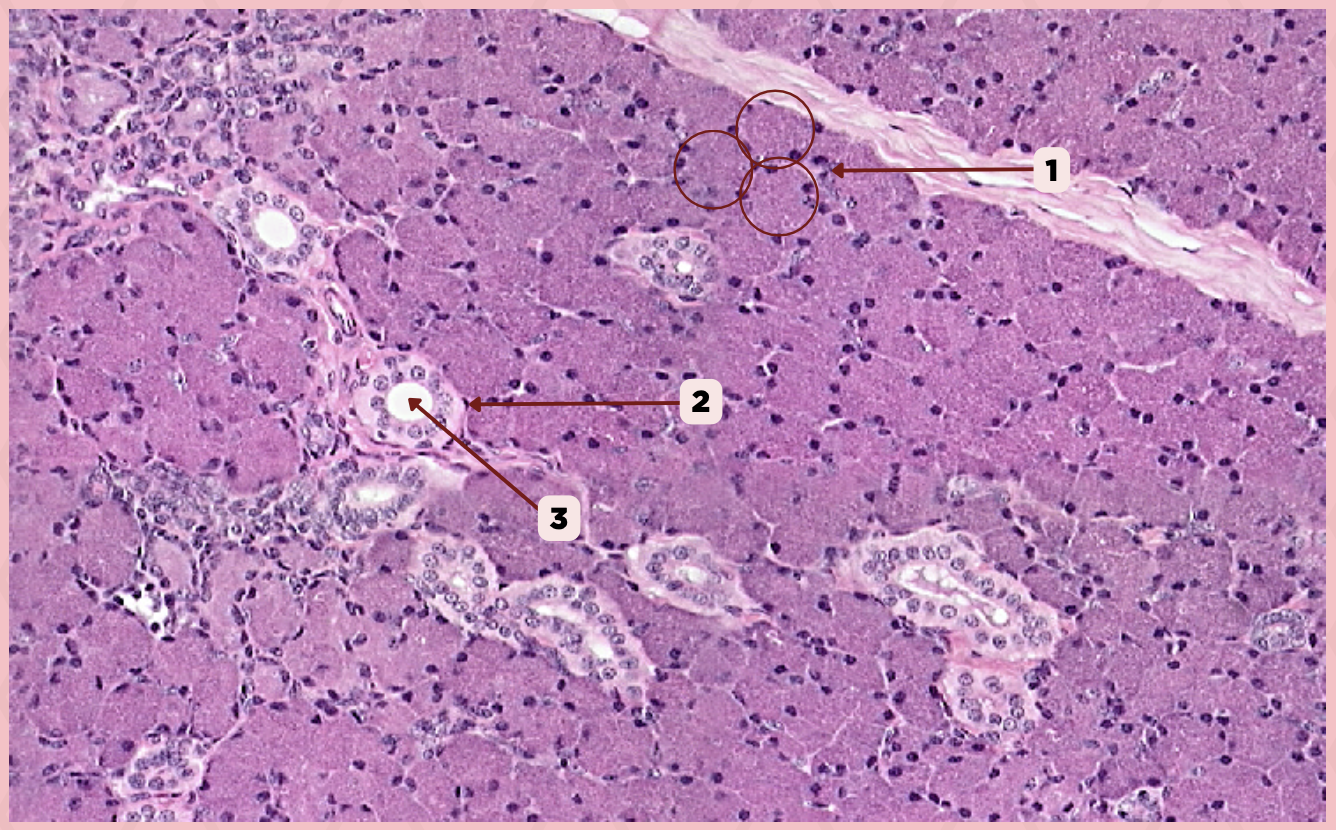

Parotid

Identify the specimen.

Capsule

Identify the structure labeled as 1.

Septa

Identify the structure labeled as 2.

Lobule

Identify the structure labeled as 3.

Lymph Node

Identify the structure labeled as 4.

Parotid

Identify the specimen.

Vein

Identify the structure labeled as 1.

Artery

Identify the structure labeled as 2.

Nerve

Identify the structure labeled as 3.

Interlobular Septa

Identify the structure labeled as 4.

Interlobular Duct

Identify the structure labeled as 5.